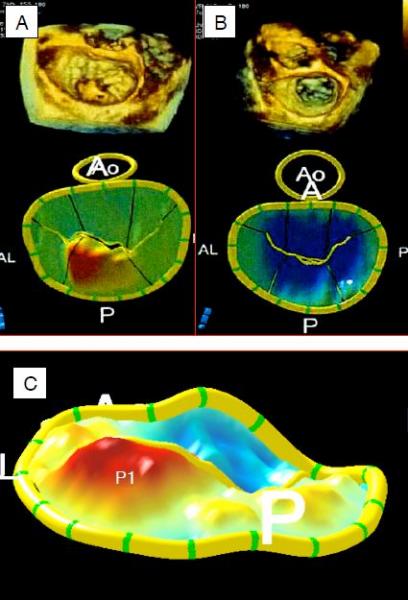

Le mode tridimensionnel comble substantiellement les lacunes du 2D pour l'examen des structures mitrales et pour les calculs hémodynamiques. Les modes 3D en temps réel sont précieux pour visualiser l'appareil mitral en mouvement, y compris dans l'image "en-face" de la valve où celle-ci est affichée comme vue depuis l'OG (vue chirurgicale); l'image est positionnée de manière à avoir la valve aortique à 10 heures et l'appendice auriculaire gauche à 10 heures [25]. Depuis cette position rétrocardiaque à mi-œsophage, la sonde ETO peut être avancée en position transgastrique et y offrir une excellente image de l'appareil sous-valvulaire. Le 3D en temps réel (X-plane, live-3D et zoom) est particulièrement utile pour diriger les cathéters dans les interventions percutanées [35]. A partir de l'imagerie 3D full-volume, il est possible de procéder à des découpes (cropping) selon n'importe quel plan et de faire ressortir certains éléments (feuillets, anneau) en supprimant les tissus voisins. Grâce à des algorithmes adaptés, on peut ainsi mesurer directement la surface de l'orifice de régurgitation, la surface des feuillets, le volume des prolapsus, le volume de tente, la non-planarité de l'anneau, la localisation des muscles papillaires, la quantification volumétrique du jet d'IM, etc. L'évaluation volumétrique du VG indépendamment de toute approximation géométrique permet un calcul fiable du volume systolique et de la fraction d'éjection, mais dépend de l'acuité de la détection automatique des contours de la cavité ventriculaire [7,19,25].

La superposition du jet couleur sur l'imagerie 3D full-volume définie par une échelle de gris fixe permet une fréquence d'acquisition de 30-40 Hz donnant environ 12 images par systole; en reconstruction off-line, il est possible de faire passer le plan de coupe par la zone la plus étroite de la vena contracta et d'en mesurer la surface, quelle que soit sa forme mais pour autant qu'on soit bien perpendiculaire au flux [6]. Une nouvelle technologie d'optimisation du champ de l'image permet le calcul automatique de la surface du PISA et de la SOR à partir d'un examen 3D avec Doppler couleur en temps réel; la corrélation avec les calculs manuels est excellente et la variabilité est très diminuée, parce que le système ne présuppose pas que le PISA soit hémisphérique mais calcule la surface réelle quelle que soit sa forme [41]. Les programmes semi-automatiques de modelage paramétrique permettent d'extraire des sutructures comme l'anneau et les feuillets mitraux à partir des données de full-volume; on peut ensuite y faire une série de mesures (Figure 11.78) [35,40].

- Diamètre antéro-postérieur de l'anneau: normal < 1.6 cm/m2 (Barlow: > 2.5 cm/m2);

- Surface de l'anneau: normal < 5 cm2/m2 (Barlow: > 7.5 cm2/m2);

- Surface du feuillet antérieur: normal < 2.75 cm2/m2 (Barlow: > 4.75 cm2/m2);

- Diamètre intercommissural: normal < 1.8 cm/m2, sans modification au cours de la systole (Barlow > 1.8 cm/m2, avec élargissement en télésystole);

- Elévation de l'anneau mitral (hauteur de selle): normal 1 cm (Barlow < 0.8 cm);

- Hauteur de ballonnisation: dégénérescence fibro-élastique < 1 cm, Barlow > 1 cm;

- Volume de ballonnisation: dégénérescence fibro-élastique < 1.15 cm3, Barlow > 1.15 cm3;

- Volume de tente (IM secondaire sévère: > 1.5 cm3).

Figure 11.78: Reconstructions 3D de la valve et de l'anneau mitral; images en full-volume en haut et images paramétriques de l'anneau et des feuillets mitraux en-bas. A: prolapsus de P2 (IM type II). B: IM restrictive (type IIIb). L'orifice de régurgitation n'est nullement circulaire comme le présuppose les calculs classiques, mais il a clairement une forme de fente. C: image agrandie d'un prolapsus de P1. Les parties teintées en bleu sont situées en-dessous du plan de l'anneau, celles teintées en rouge sont situées au-dessus du plan de l'anneau [extrait de: Poelaert JI, Bouchez S. Perioperative echocardiographic assessment of mitral valve regurgitation: a comprehensive review. Eur J Cardio-Thor Surg 2016; 50:801-12].